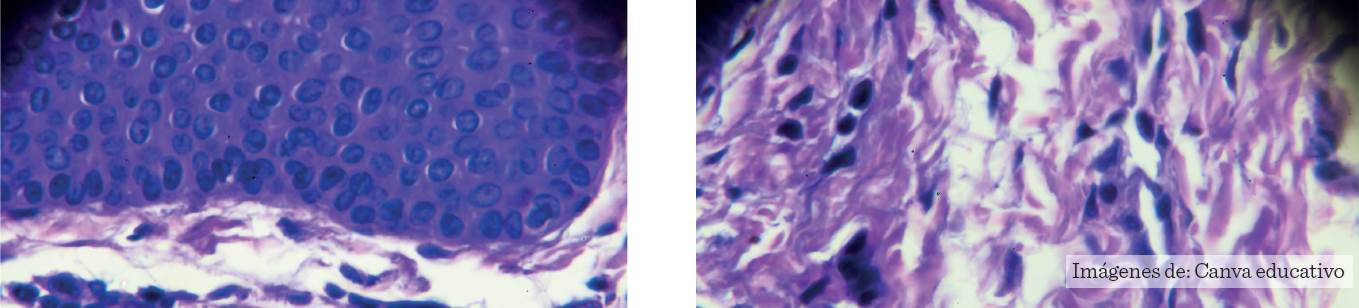

Al igual que las lesiones precursoras del cérvix, las lesiones de ano cuentan con atipias celulares microscópicas hasta grados diversos de displasia, antes de progresar a un cáncer invasor (Elorza y col., 2016). Por lo anterior, la NIA, que es el homólogo de NIC, tiene cierta predilección por la zona de transición epitelial (70 % a 80 %), esto debido a que ambas regiones tienen el mismo origen embriológico, compartiendo características histológicas similares (Nelson y Benson, 2017).

Figura 1 Historia natural de infección por VPH anal y cervical, con progresión a lesiones precursoras y cáncer. Neoplasia intraepitelial cervical (NIC) y Neoplasia inraepitelial anal (NIA), NIC 2 y 3 (Neoplasia intraepitelial cervical de alto grado) y NIA 2 y 3 (Neoplasia intraepitelial anal de alto grado. VPH-AR (Virus del Papiloma Humano de alto riesgo). Modificado a partir de Fraga-Campo, 2010.